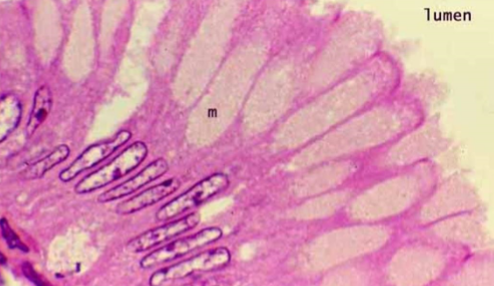

Label the following image

State 3 anatomical features of small intestine to increase surfacea area

What is meant by the brush border?

The microvilli (increases surface area but also contains digestive enzymes)